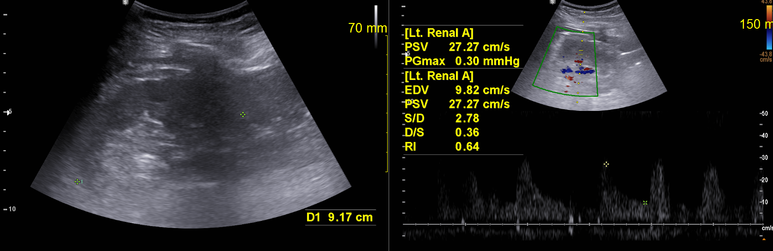

RI 정상범위임을 확인하였으나 양측 신장이 9-10cm로 크기가 약간 감소하여있다. 오래된 혈압에 의한 신장기능 저하를 확인할 필요가 있다.